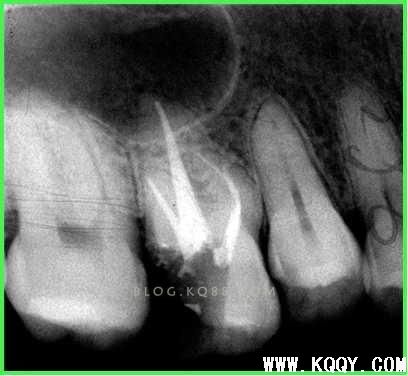

镍钛机扩:

冠向下法

SX G S1 S2 根管上2/3段预备。F1 F2 对根尖切削能力强,不要反复提拉,1次即可根管内停留1秒,过多切削会破坏根管原有形态破坏抗力形。

弯曲根管采用手动机括相配合的方式进行